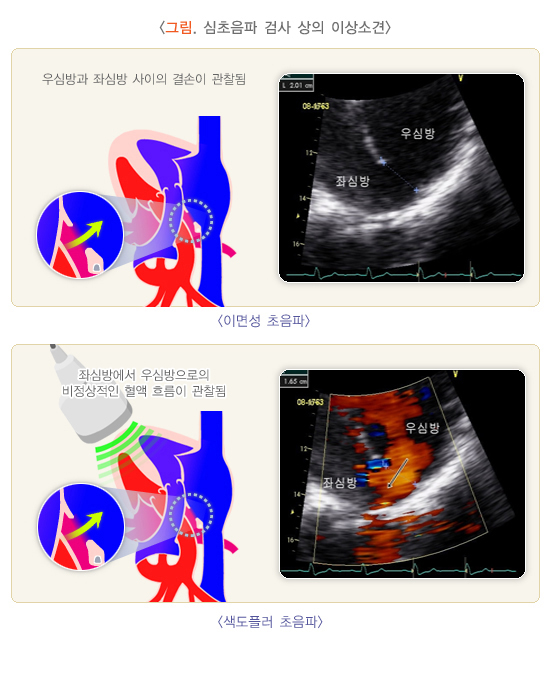

- 일반 초음파 검사 (Ultrasound)

- 초음파를 인체에 쏘아 반사된 음파를 이용해 장기나 조직의 해부학적 구조를 영상으로 확인하는 검사입니다.

- 구조적인 변화, 장기 크기, 형태, 종양, 물혹 등 해부학적 정보에 초점이 맞춰집니다.

- 혈류나 혈액의 움직임에 대한 정보는 제공하지 않습니다.

- 도플러 초음파 검사 (Doppler Ultrasound)

- 일반 초음파의 원리에 도플러 효과를 적용한 검사로, 움직이는 혈액의 속도와 방향을 실시간으로 측정할 수 있습니다.

- 혈관 내 혈류의 특성을 분석해 혈류가 정상적으로 흐르는지, 역류나 협착이 있는지 평가할 수 있습니다.

- 혈관의 기능적 상태를 파악하는 데 중요한 역할을 하며, 하지정맥류, 동맥 협착, 혈전 등 혈관 질환 진단에 쓰입니다.

요약하면, 일반 초음파는 신체 내부 구조를 영상으로 보여주는 데 중점을 두고,

도플러 초음파는 혈관 내 혈액의 흐름과 속도, 방향 등 혈류역학적 정보를 측정하는 검사입니다.

도플러 초음파는 혈관 질환 등의 진단에 필수적인 검사법입니다.